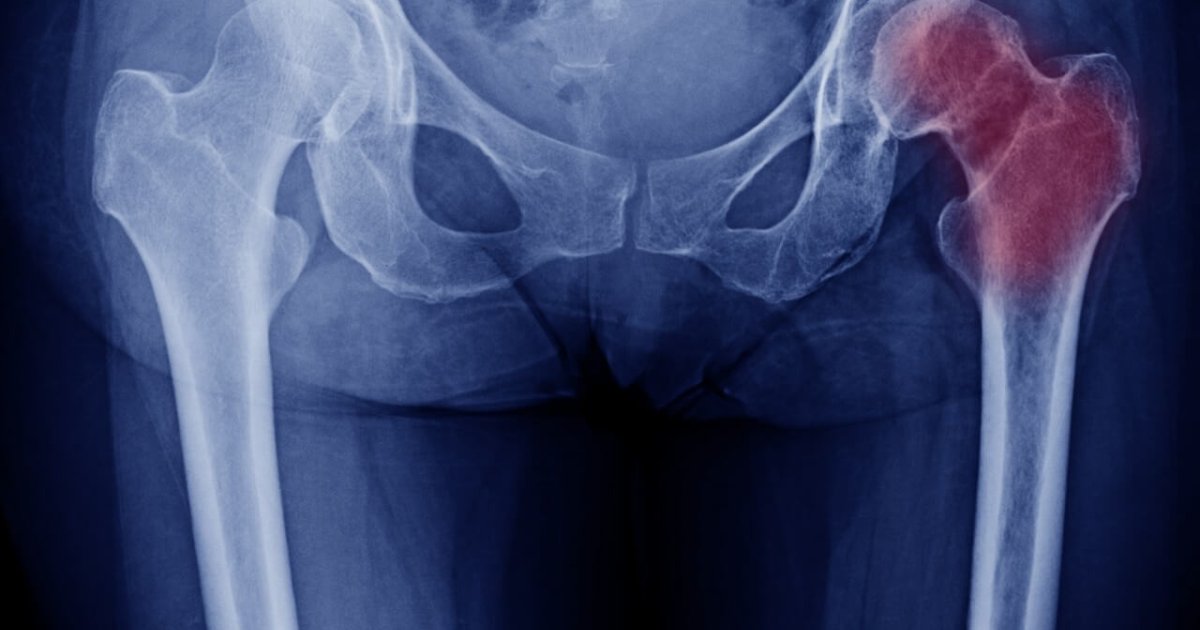

A osteonecrose, também conhecida como necrose avascular, é uma condição que afeta os ossos. Ela ocorre quando uma diminuição do suprimento sanguíneo leva à morte do tecido ósseo (infarto ósseo), resultando em dor, inflamação e, em casos mais avançados, destruição (colapso do osso afetado). Geralmente, a articulação do quadril e do joelho são as áreas mais comumente afetadas pela osteonecrose.

O tratamento da osteonecrose cabeça femoral visa aliviar a dor, melhorar a função da articulação e retardar ou impedir a progressão da doença. As opções de tratamento variam dependendo da causa subjacente, da localização da osteonecrose e do estágio da doença. Algumas abordagens utilizadas incluem: